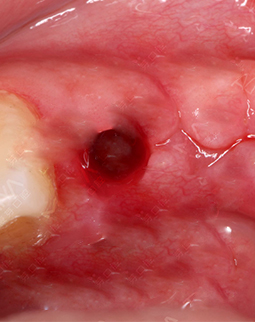

左边是我种牙之前,缺牙很久了,所以这个牙床口长好了。右边是我的种植牙创口,大小和牙根差不多,这个很容易理解,因为种植体就是人造牙根,得有个洞才能把它埋进去,我种牙的创口很小了,基本是微创的,比起过去的切开牙龈种牙好太多了!所以大家不用太担心,你选个好的医院和医生,种植牙还是很靠谱的。